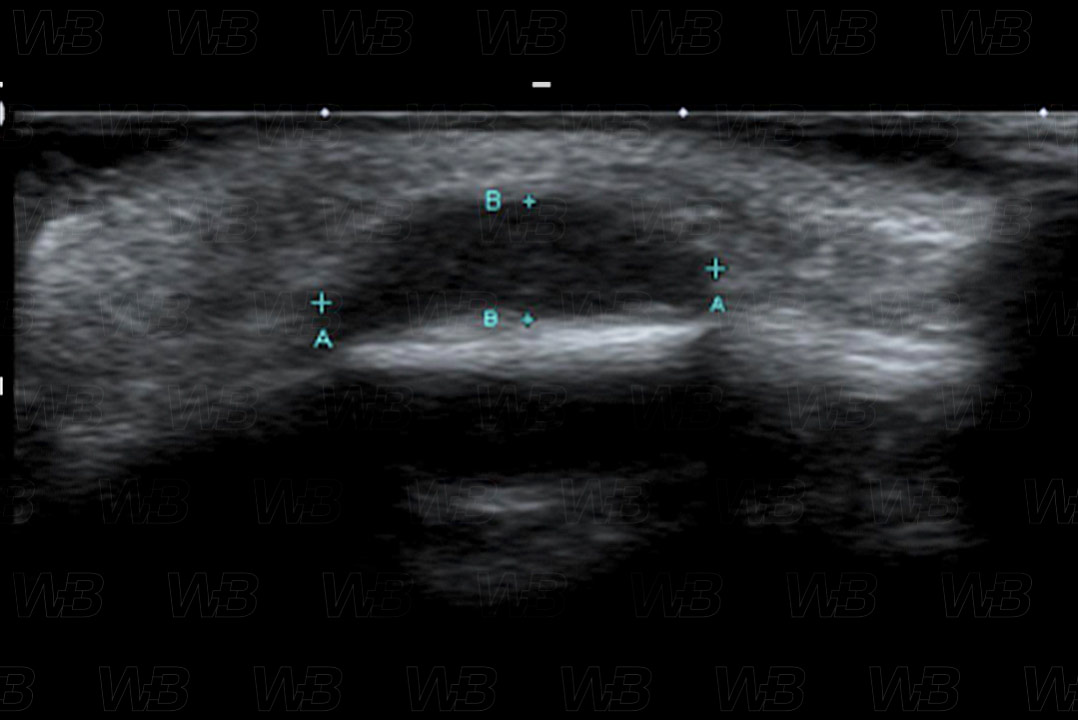

Texto alternativo para a imagem Figura 3. Crédito: Dra. Elazir Mota - Rio de Janeiro/RJ

Descrição da lesão: Ultrassonografia de partes moles (figuras 3 e 4). Cisto dermoide, menino de 2 anos, com lesão firme no couro cabeludo. A projeção longitudinal sobre a região frontal mostra lesão hipoecoica, bem definida, que expande o espaço diploico do calvário.

• Ultrassonografia das partes moles: Exame de escolha . A ultrassonografia mostra lesão hipoecoica e bem definida, frequentemente na calota craniana, com borda hiperecoica, sem vascularização ao estudo com Doppler colorido;